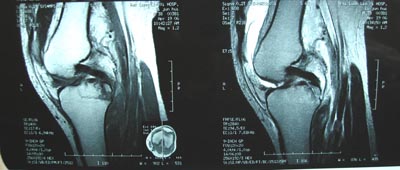

标题: 现将mri结果公布

手术证实是后交叉韧带胫骨附着处撕脱骨折。

术中用可吸收螺钉固定。